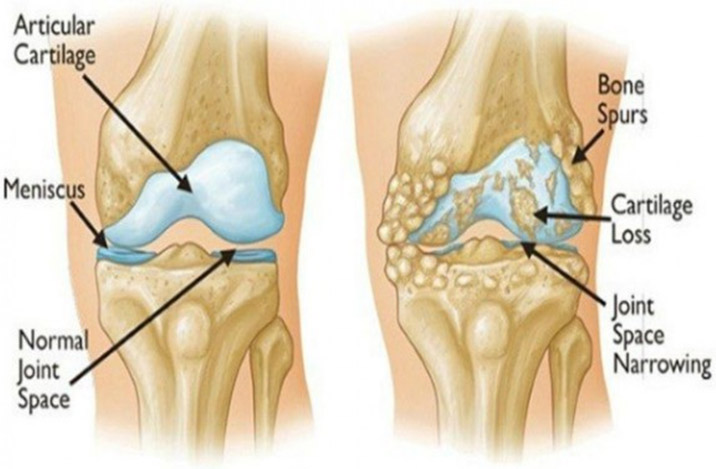

Various causes like aging or wear and tear of cartilage lead to knee problems like knee pain, swelling or stiffness that hampers your day to day life. Other factors causing knee conditions may include : irritation of cartilage in the inner side of patella which is commonly known as Kneecap, or also build up of fluid in the knee area.

A total knee replacement surgery is a surgery to replace an entire knee joint with an artificial one. It is also known as an arthroplasty. The most common reason for this surgery is osteoarthritis, which is a degenerative disease that affects the joints.